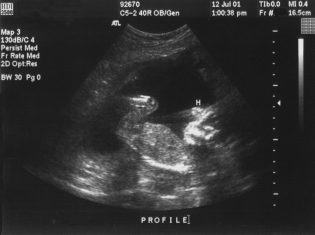

About one in 160 pregnancies nationwide result in stillbirth, the death of the baby after 20 weeks of gestation. The risk factors that have already been known to contribute, such as obesity, diabetes, high blood pressure or a previous pregnancy loss, only account for a small percentage of stillbirths.

The SCRN went on to do comprehensive medical evaluations of 512 stillborn babies to identify the causes of death in further detail, examining the placenta and doing an autopsy of the fetus.

Scientists identified a probably cause of death in 61 percent of the cases, and a probable or possible cause in 76 percent. Pregnancy or birth-related complications contributed to the largest proportion of stillbirths (29 percent), including preterm labor, premature rupture of the amniotic sac and abruption of the placenta.